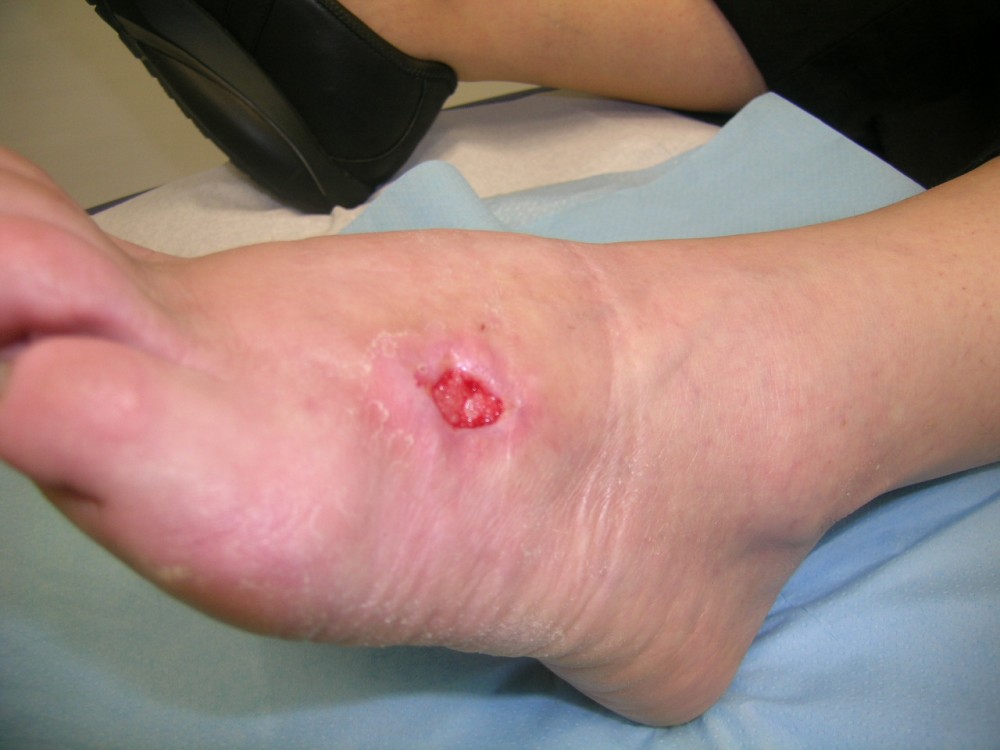

Motivo de consulta: Paciente que acude el 12-8-2013 a nuestro centro asistencial con una fuerte contusión en pie izquierdo. Es trasladada por un compañero de trabajo. Tras ser vista y realizada exploración radiológica negativa. Se realiza vendaje compresivo y se le deja con carga relativa de EI Izda. con ayuda de bastones ingleses. Tto. analgésico y reposo. A la semana (19-8-2013) en la revisión refiere dolor intenso en antepié izquierdo desde hace 3 días. El vendaje aparece manchado. Al retirar vendaje aparece zona necrosada en cara externa del antepié izquierdo. Tras interconsulta con cirugía plástica se decide realizar desbridamiento bajo A/L. Antecedentes personales: -Alérgica a METAMIZOL y PENICILINA. - No refiere enfermedades. - Vacunada Difteria- Tétanos. - No fumadora. - No patología ginecológica. Ha tenido 1 parto a los 26 años (sin complicaciones)

• 8. Higiene / Integridad piel y mucosas: Herida ulcerada y necrosada en cara externa de antepie izquierdo de 5 cm. de diámetro y 2 cm. de profundidad

La paciente acudió el 12-8-2013 con una contusión fuerte en antepié izquierdo que fué tratada con inmovilización, analgesia y tratamiento anticoagulante con heparina de bajo peso molecular. y descarga de la extremidad. A la semana acude a revisión presentando dolor intenso y zona de necrosis en supercie de contusión. El mismo día de revisión (19-8-2013) se realiza consulta con cirujano que realiza desbridamiento quirúrgico bajo A/L quedando una herida con buen fondo de granulación de 5 cm. de diámetro x 2 cm. de profundidad. Se mantiene tratamiento anticoagulante, se refuerza tratamiento analgésico y se instaura tratamiento antibiótico. Se pautan 3 curas semanales. Se hace control semanal de todos indicadores retirando el tratamiento antibiótico a la 3ª semana, se suspende el tratamiento anticoagulante a la 4ª semana, se suspende el tratamiento analgésico a la 7ª semana. Produciéndose la curación de la herida a la 8ª semana. Queda pediente de revisión al año del accidente por posibles secuelas cicatriciales.